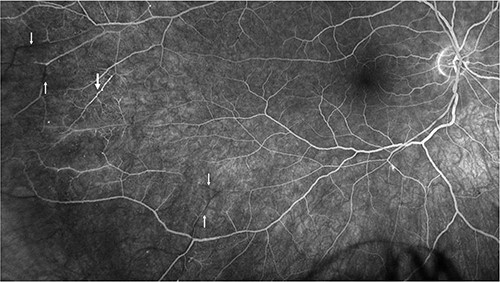

Repeat MRI at this time demonstrated several small T2 hyperintense foci within the deep white matter tracts of both cerebral hemispheres, the corpus callosum, and the thalamic and basal ganglion in addition to the typical linear ‘spoke’ lesions within the roof of the corpus callosum (Fig. 2). Fluorescein fundus angiography demonstrated multiple BRAOs and arterial wall hyperfluorescence (AWH) in the infratemporal region of the right eye, while the examination of the left eye remained normal (Fig. 3).

Fluorescein angiography of the right eye illustrating pathognomonic findings of BRAOs (thin arrows) and AWH (thick arrow).